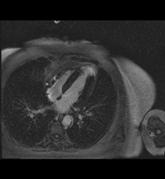

Das Klinikum Ludwigshafen verfügt über einen Kardio-CT der neuesten Generation: Das 128-Zeilen-Gerät ermöglicht eine äußerst präzise Untersuchungsmethode zur Darstellung der Herzkranzgefäße des schlagenden Herzens.

Die koronare Herzerkrankung (KHK) ist eine der häufigsten Erkrankungen in der westlichen Welt. Bei dieser Erkrankung führen Kalkablagerungen an der Gefäßwand (Arteriosklerose) zur Verengung des betroffenen Gefäßes. Diese Engstellen (Stenosen) vermindern die Blutversorgung des Herzmuskels. Kommt es mit dem Fortschreiten der KHK zum Gefäßverschluss, entsteht ein Herzinfarkt.

Die Computertomografie des Herzens (Kardio-CT) ist eine Methode, die frühen Stadien der KHK zu erkennen, bzw. eine KHK mit an Sicherheit grenzender Wahrscheinlichkeit ausschließen zu können.

Prinzipiell ist die Kardio-CT eine Computertomografie (CT), also eine Röntgenuntersuchung, bei der die Röntgenröhre spiralartig um den Patient rotiert. Das Besondere ist die enorme Leistungsfähigkeit der CT, bei der mehrere, sehr dünne Schichten pro Umdrehung gleichzeitig aufgenommen werden.

In Ludwigshafen verwenden wir einen CT der neuesten Generation der Firma Siemens, mit dem wir 128 Schichten pro Umdrehung aufnehmen. Auf diese Weise lässt sich das gesamte Herz mit nur vier bis fünf Umdrehungen erfassen. Für Sie bedeutet das, dass wir Ihre Herzkranzgefäße in der derzeit bestmöglichen Auflösung und mit geringst möglicher Strahlenbelastung darstellen können.